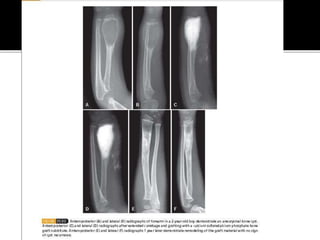

 A.K.A Campanacci disease

 Ossifying fibroma of long bones

 Common 2nd-3rd decade of life – usually

affecting the tibia and fibula

 Presentation – Asymptomatic unless there’s a

pathological fracture – anterior bowing.

 Radiologically – Multicentric radiolucent

lesions of the cortex of the tibia

 Histologically – Irregular trabeculae with

prominent osteoblastic rimming in a loose

fibrous stroma

 Treatment – Observation, Fractures usually

non-operatively, deformity correction.